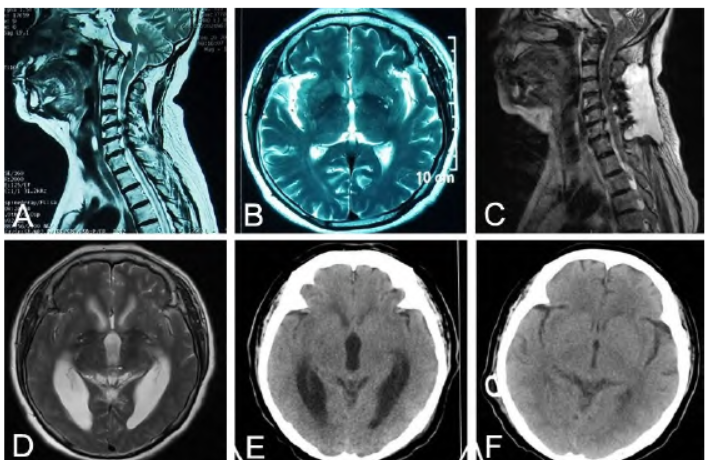

,双侧瞳孔等大等圆,直径2.5 mm,对光反射灵敏;四肢肌力Ⅳ级,仅可在搀扶下站立,感觉及共济检查不合作。头颈MRI显示幕上脑室扩张,小脑扁桃体下疝,颅底凹陷,颈部皮下积液(图1C、1D)。

较前变差,昏睡,进食差,复查头CT显示脑室较前明显扩张(图1E),遂行脑室-腹腔分流术。术后意识状态明显改善,小便自知可控,可独立行走,分流术后10 d复查头CT显示脑室形态正常(图1F)。分流术术后半年随访,患者神志清楚,言语语利,生活自理,大小便自知可控,可独立上下楼,记忆力理解力正常,肢体麻木症状未再发作。

图1 小脑扁桃体下疝畸形颈椎管减压术后并发脑积水影像学表现。A、B. 颈椎管减压术前MRI显示小脑扁桃体下疝低于枕骨大孔约7 mm,颅底凹陷,颈椎管狭窄,脑室形态正常;C、D. 颈椎管减压术后颈椎MRI显示颈部皮下积液,全脑室系统扩张;E. 枕大孔减压术后1个月头部CT显示全脑室系统扩张;F. 脑室-腹腔分流术后10 d复查头部CT显示脑室系统恢复正常